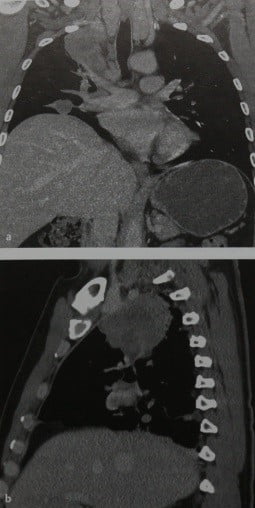

Рентгеновские снимки опухоли Панкоста